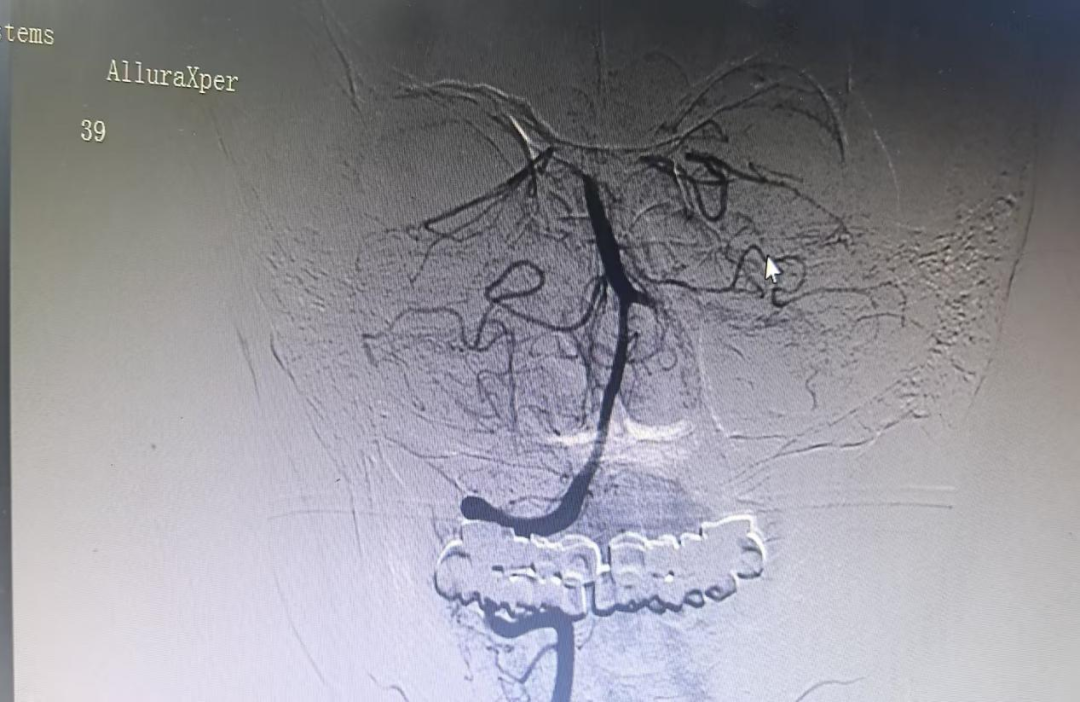

手术室内,神经介入团队沉着应战,凭借丰富的临床经验与娴熟的操作技巧,经股动脉穿刺,精准置入导管,在数字减影血管造影(DSA)的实时引导下,穿过复杂的血管通路,直达闭塞部位。面对黏连紧密的血栓,团队精准操控取栓支架,精准抓取、缓慢回撤,一气呵成成功取出血栓。造影影像清晰显示,闭塞的基底动脉即刻复通,脑部供血迅速恢复,手术全程两小时,为患者后续康复筑牢了关键基础。